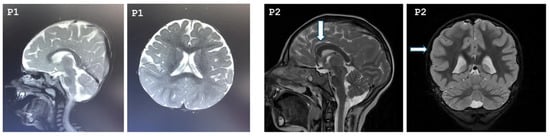

Our study included seven patients diagnosed with MCPH3 from six different families. Three patients were females, and four were males. All patients were born to consanguineous parents who were first-degree cousins. The mean age of the patients was 7 years 3 months. Two of the patients were born late preterm, and all patients had birth weight and length appropriate for their gestational age. Compared to their motor skills, their speech development was more delayed. Two of the patients exhibited neuromotor developmental delay, and speech delay was noted in six patients. Five of the patients had learning difficulties and were receiving special education; evaluation was inconclusive for one patient (Patient 1) due to their young age. One patient had a history of seizures. On physical examination, all patients were found to have severe microcephaly, with a mean head circumference of −6.1 SDs (range: −7.9 to −3.7 SDs). Three of the patients (Patients 1, 3, 5, 7) exhibited postnatal short stature, while two patients had growth deficiency in weight (Patients 1, 6). On dysmorphic examination, the most prominent features observed in the patients were brachycephaly, hypertelorism, epicanthus, high-arched eyebrows, high nasal bridge, and micrognathia. Other dysmorphic findings were not distinctive and appeared to be patient-specific, such as sloping forehead, synophrys, upslanting palpebral fissures, ptosis, anteverted nares, low columella, long philtrum, and thick vermilion border. Conical teeth were observed in Patients 4 and 5. Additionally, the exfoliation of primary teeth had not yet occurred in Patient 5. Cutaneous pigmentary abnormalities of varying sizes in different body regions were observed in six of the seven patients. Cranial magnetic resonance imaging (MRI) revealed diffuse parenchymal volume loss in both cerebral hemispheres in Patient 1. In Patient 2, the frontal lobes appeared smaller than normal in both hemispheres, with associated findings of hypoplastic corpus callosum, pachygyria, and absence of the pineal gland. In Patient 6, an arachnoid cyst measuring 14 mm was detected in the retrocerebellar region. MRI findings were normal in the remaining patients. The cranial MRIs of Patients 1 and 2 are shown in Figure 1.

Figure 1. Cranial MRI images of Patient 1 and Patient 2. P1: T2-weighted sagittal and axial cranial MRI of Patient 1 demonstrating bilateral diffuse cerebral atrophy. P2: The arrows indicate a hypoplastic corpus callosum and pachygyria, respectively, in Patient 2.

The vast majority of patients with MCPH3 do not exhibit distinctive dysmorphic facial features. In a subset of patients, the most notable findings include a sloping forehead, hypertelorism, epicanthus, and a high nasal bridge [10,11,13,24]. In our patients, hypertelorism, epicanthus, and a high nasal bridge were the most prominent facial features, with the additional observation of high-arched eyebrows, a finding not previously reported in the literature. Nevertheless, as noted above, distinguishing patients based on phenotype alone is rarely possible. In most patients with MCPH3, neuromotor development, including head control, independent sitting, and walking, is appropriate for age; however, mild delays have been observed in some individuals [25,26]. Mild delays in neuromotor development were present in two of our patients (P1 and P3). In nearly all patients with MCPH3, mild to moderate intellectual disability is present, while severe impairment is observed in only a small number of cases [10,26,27]. In our cohort, one patient could not be reliably assessed due to young age, while another 4-year-old patient (P4) had no intellectual disability and had never received special education; however, no formal testing had been performed. In contrast, his older sister, carrying the same mutation, had intellectual disability and was receiving special education. Cranial MRI findings in MCPH3 patients include reduced brain volume, gyral simplification, agenesis, hypoplasia, or dysgenesis of the corpus callosum, and enlargement of the cisterna magna. In the study by Erdogan et al. (2025) [10], previously unreported findings such as an arachnoid cyst and colpocephaly were documented. Nasser et al. (2020) [26] identified inter-hypothalamic adhesion (IHA) in 5 of 7 patients; however, none of their patients exhibited signs suggestive of hypothalamic dysfunction, such as micropenis, diabetes insipidus, or hypertension. IHA has not been reported in any MCPH3 patient prior to these observations. Nevertheless, when particularly thin or small, IHA may not always be detectable on routine brain MRI. Therefore, high-resolution imaging protocols with thin slices should be employed. All of our patients underwent cranial MRI, with pathological findings detected in only three patients. In Patient 1, diffuse parenchymal volume loss was observed in both cerebral hemispheres, whereas Patient 2 presented with reduced frontal lobe volumes, hypoplastic corpus callosum, pachygyria, and absence of the pineal gland. To the best of our knowledge, pachygyria and absence of the pineal gland have not been previously reported in other MCPH3 patients. In Patient 6, a retrocerebellar cyst measuring 14 mm was detected, similar to the finding reported by Erdogan et al. (2025) [10]. These findings all suggest that cranial involvement in MCPH3 is likely heterogeneous. To the best of our knowledge, seizures have been reported in 26% of patients with MCPH3 in the literature, including generalized tonic–clonic seizures and infantile spasms [10,11,12,13,14,18,23,24,25,27,28,29,30,31,32]. Consistent with the literature, one of our patients had generalized tonic–clonic seizures that began at the age of four. Only a small number of MCPH3 patients in the literature have undergone cranial MRI. Therefore, we could not obtain sufficient information to determine whether there is an association between seizures and cranial involvement. However, in the literature, patients with seizures who underwent cranial MRI were found to have non-specific findings—such as enhancement in the white matter, dilated ventricular system, thinning of the corpus callosum, and cerebral volume loss—which were also observed in patients without seizures [14]. Ataxia has been reported in only a few patients to date in the literature [13,26]. In the study by Jouan et al. (2016) [33], ataxia was observed in three patients with biallelic CDK5RAP2 mutations who presented with mild learning disability and agenesis of the corpus callosum, but without microcephaly. In our patient cohort, ataxia was identified in two individuals. As the mutations in our patients were novel, comparison with previously reported cases in the literature was not possible.